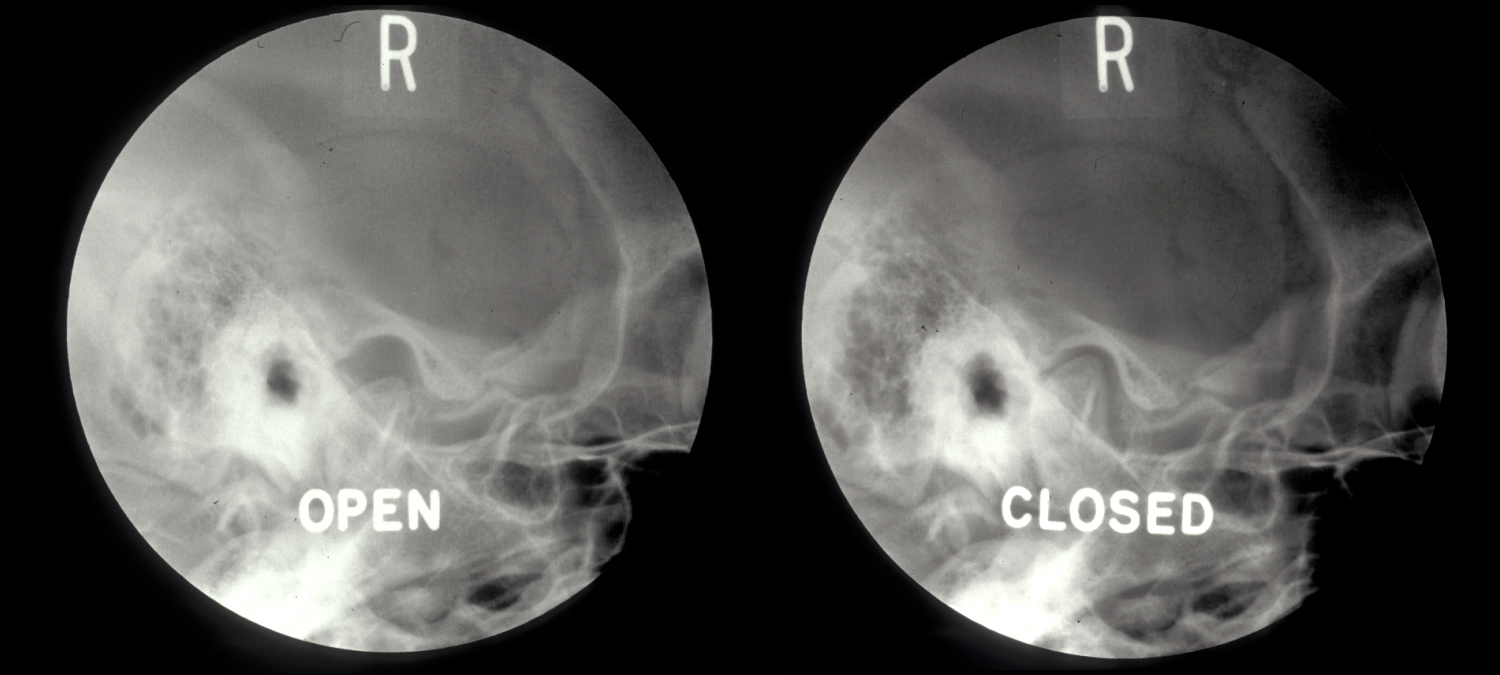

Plain X-ray radiographs are relatively easy to obtain in the clinic but they really play a minor role in detecting pathology of the jaw joint (see Figure 4 for examples).

Figure 4: Plain X-ray radiographs of a normal temporomandibular joint. Left: mouth open; right: mouth closed. Neither of these views is easy to interpret.

The temporomandibular joint is a complex three-dimensional structure and conventional radiographs only show a two-dimensional projection view, taken through one part of the joint. Only gross pathology can be picked up in this way (see Figure 5 for an example).